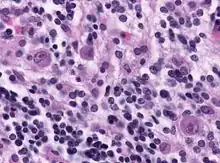

- Owl's eye appearance of the entire nucleus – a finding in Reed–Sternberg cells in individuals with Hodgkin's lymphoma.

Another particular case in 1957 found that an owl's eye appearance was found by two cells mirroring each other, producing the pattern inside the histological case study of tumors.[22] This is essentially what an owl's eye appearance is, however, the symptom did not occur from the presence of cytomegalovirus but from a unique case.